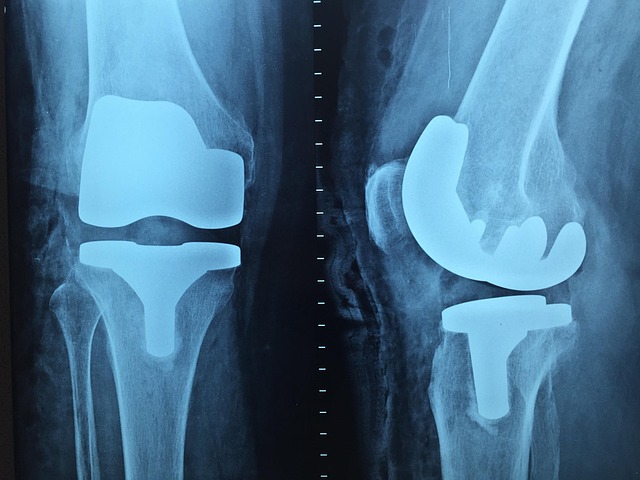

뼈는 단순한 구조물이 아닌 생체 조직으로, 끊임없이 생성과 흡수를 반복합니다.

이 과정에서 조골세포와 파골세포의 균형이 중요한데, MBP는 이 균형을 건강하게 유지시켜 줍니다.